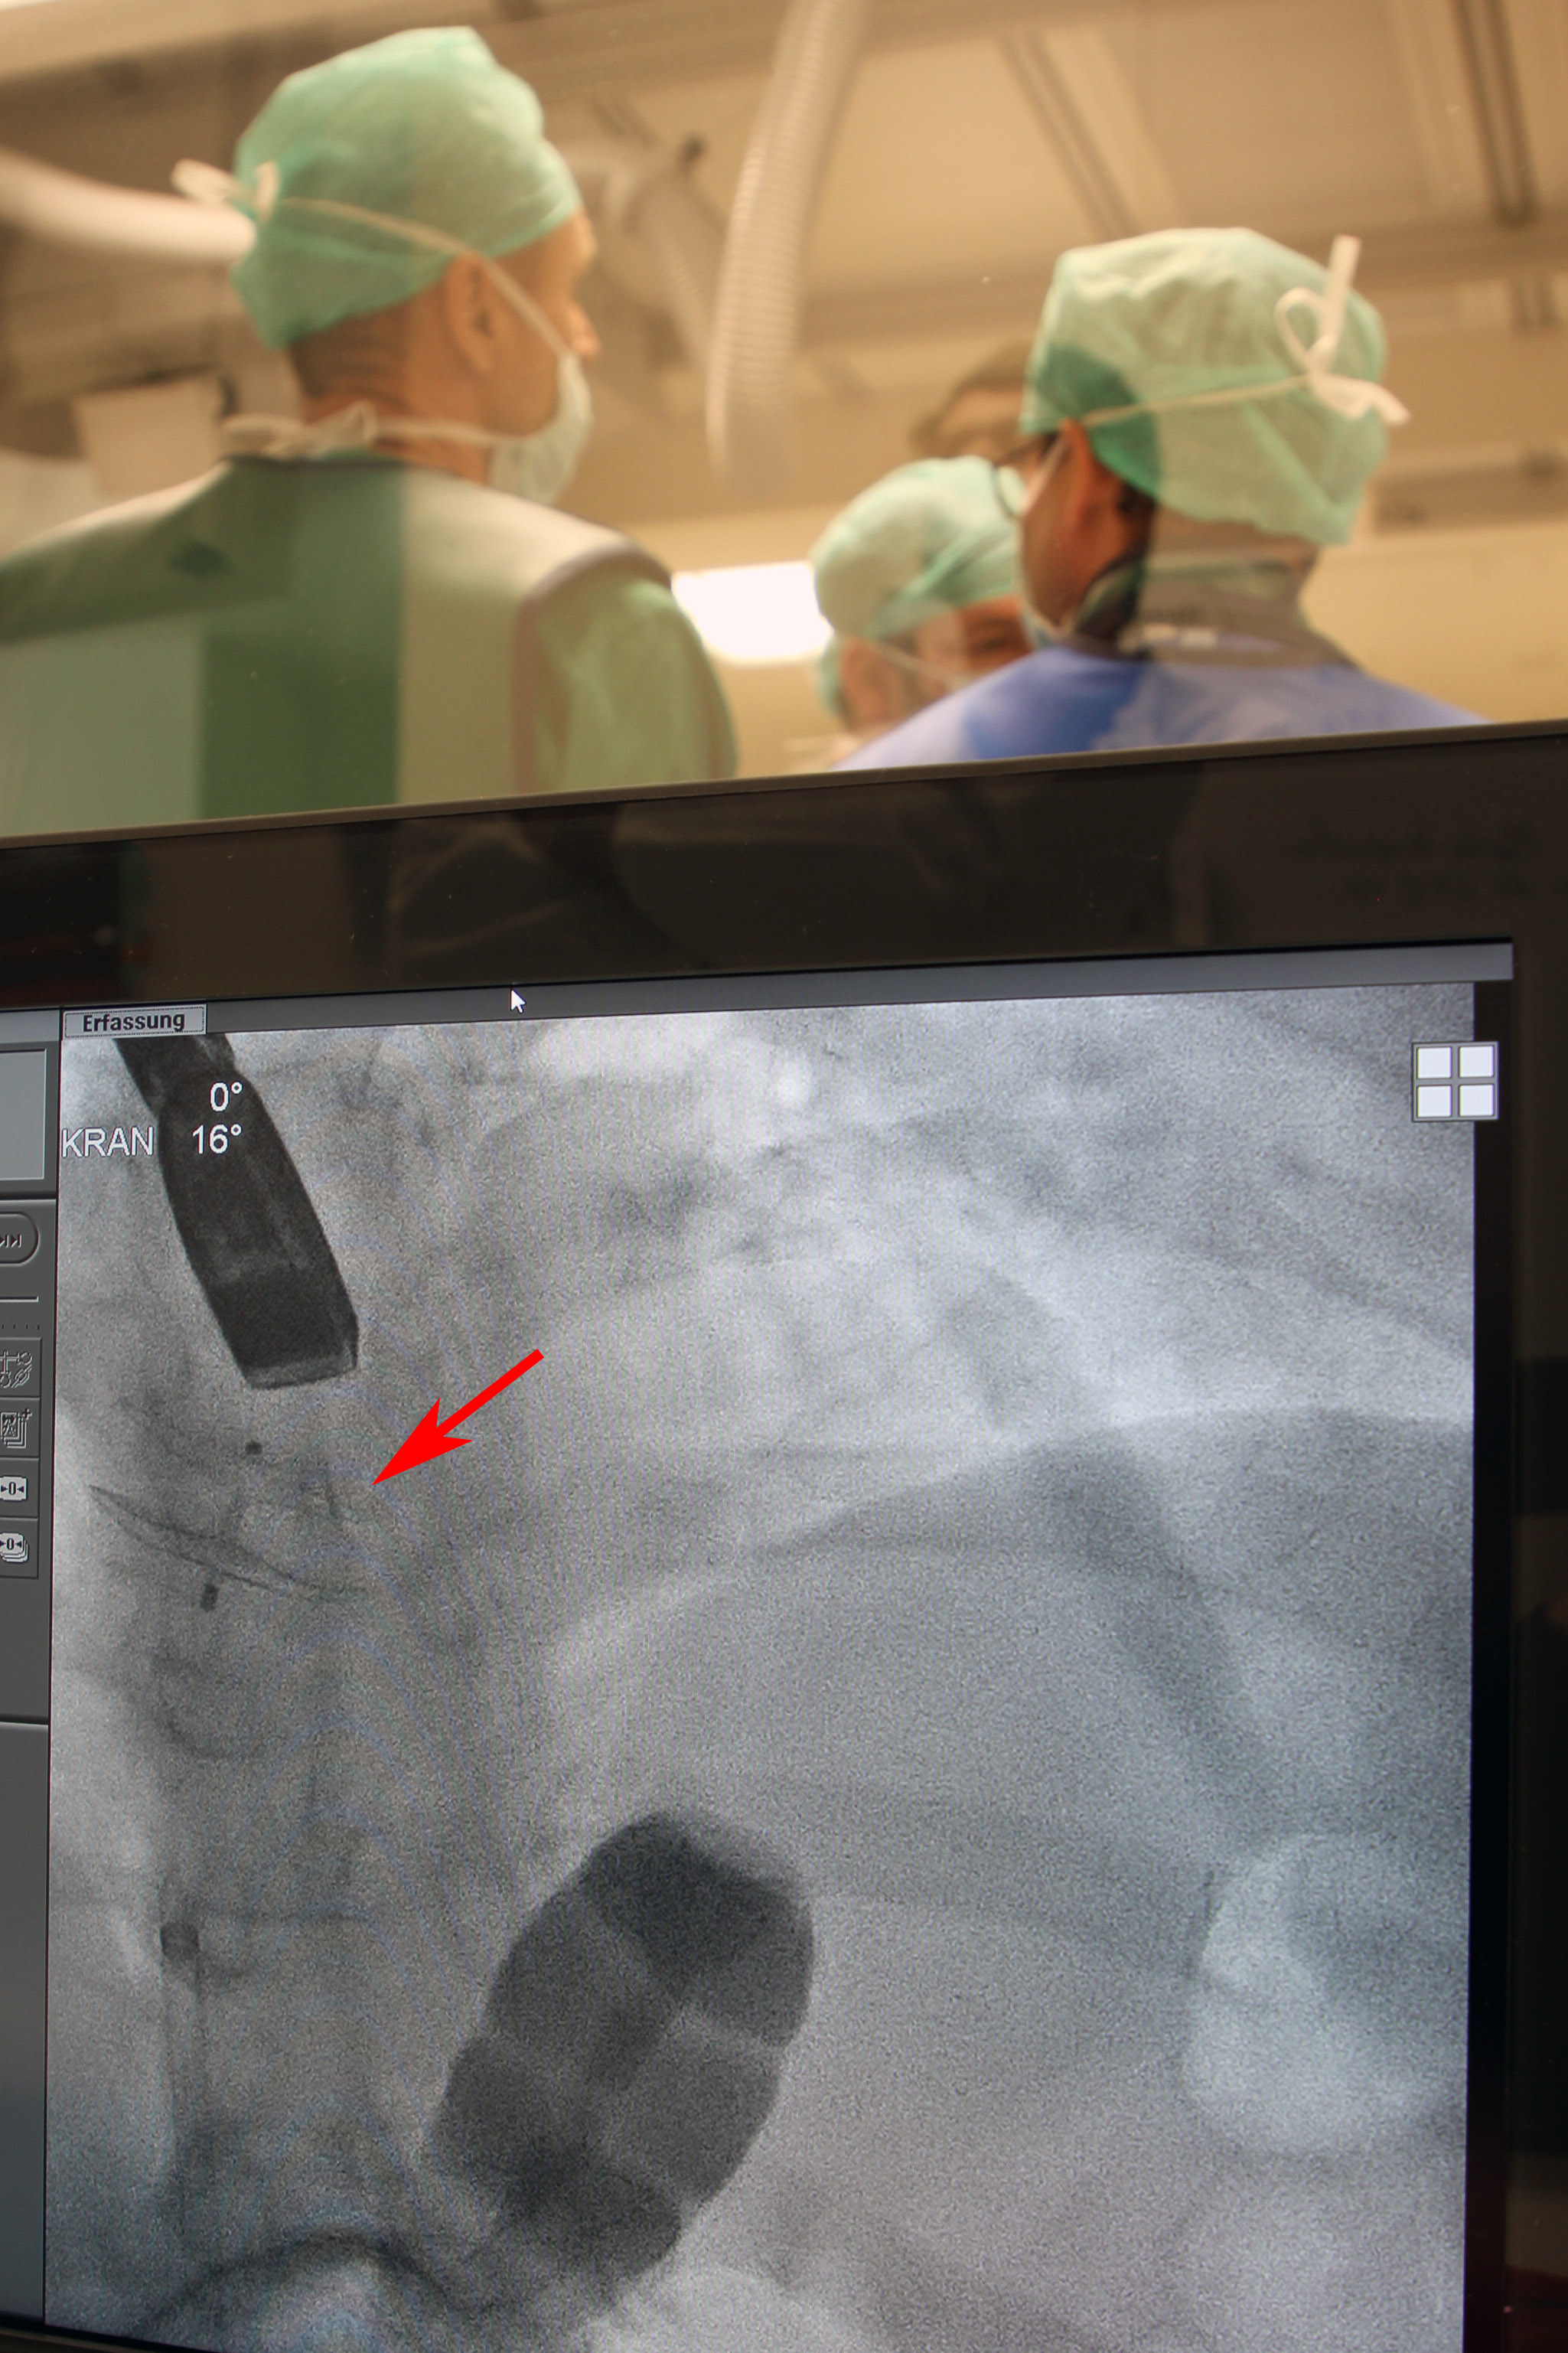

Hier ist der Amplatzer Septal Occluder bereits implantiert. In der Durchleuchtung wird die Position nochmals kontrolliert. Zudem ist auch die Ultraschallsonde zu sehen, die über die Speiseröhre eingeführt ist und ebenfalls zur Lagekontrolle verwendet wird.